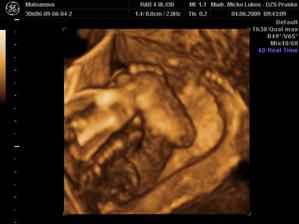

Naše druhé zlatíčko